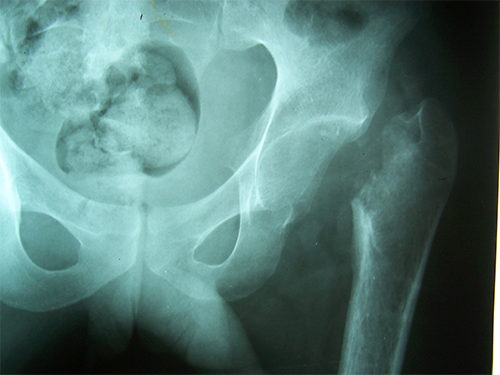

Case:4 Post Tuberculous Ankylosed Hip

Arthroscopy Surgeon in Ahmedabad|Best Trauma Surgeon in Ahmedbad

Pre-op

Arthroscopy Surgeon in Ahmedabad|Orthopedic Oncology Doctor

Post-op